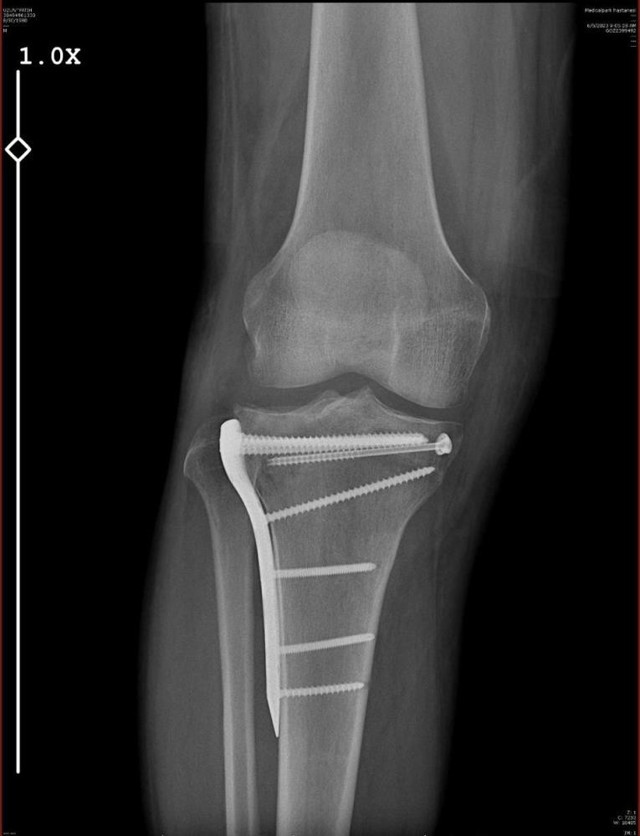

Uzun’a küfürler ederek aracı durdurmasını isteyen H.T.Ü. araçtan inip yanına gelen Fatih Uzun’a saldırmaya başladı. Aldığı darbeler sonucu bacağı iki yerden kırılan avukat geçirdiği ameliyatlar sonucunda 10 gün hastanede kaldı.

Bu olay nedeniyle hastanede 10 gün kaldım. Ciddi bir ameliyat geçirdim, ayaklarımın üstüne basamıyorum. Tedavim yaklaşık 20 hafta sürecek. Yaşanan bu olayda araç içerisinde 5 ve 9 yaşında kızlarım vardı. Çocuklarım benim sakat kalacağımdan korkuyorlar” dedi.